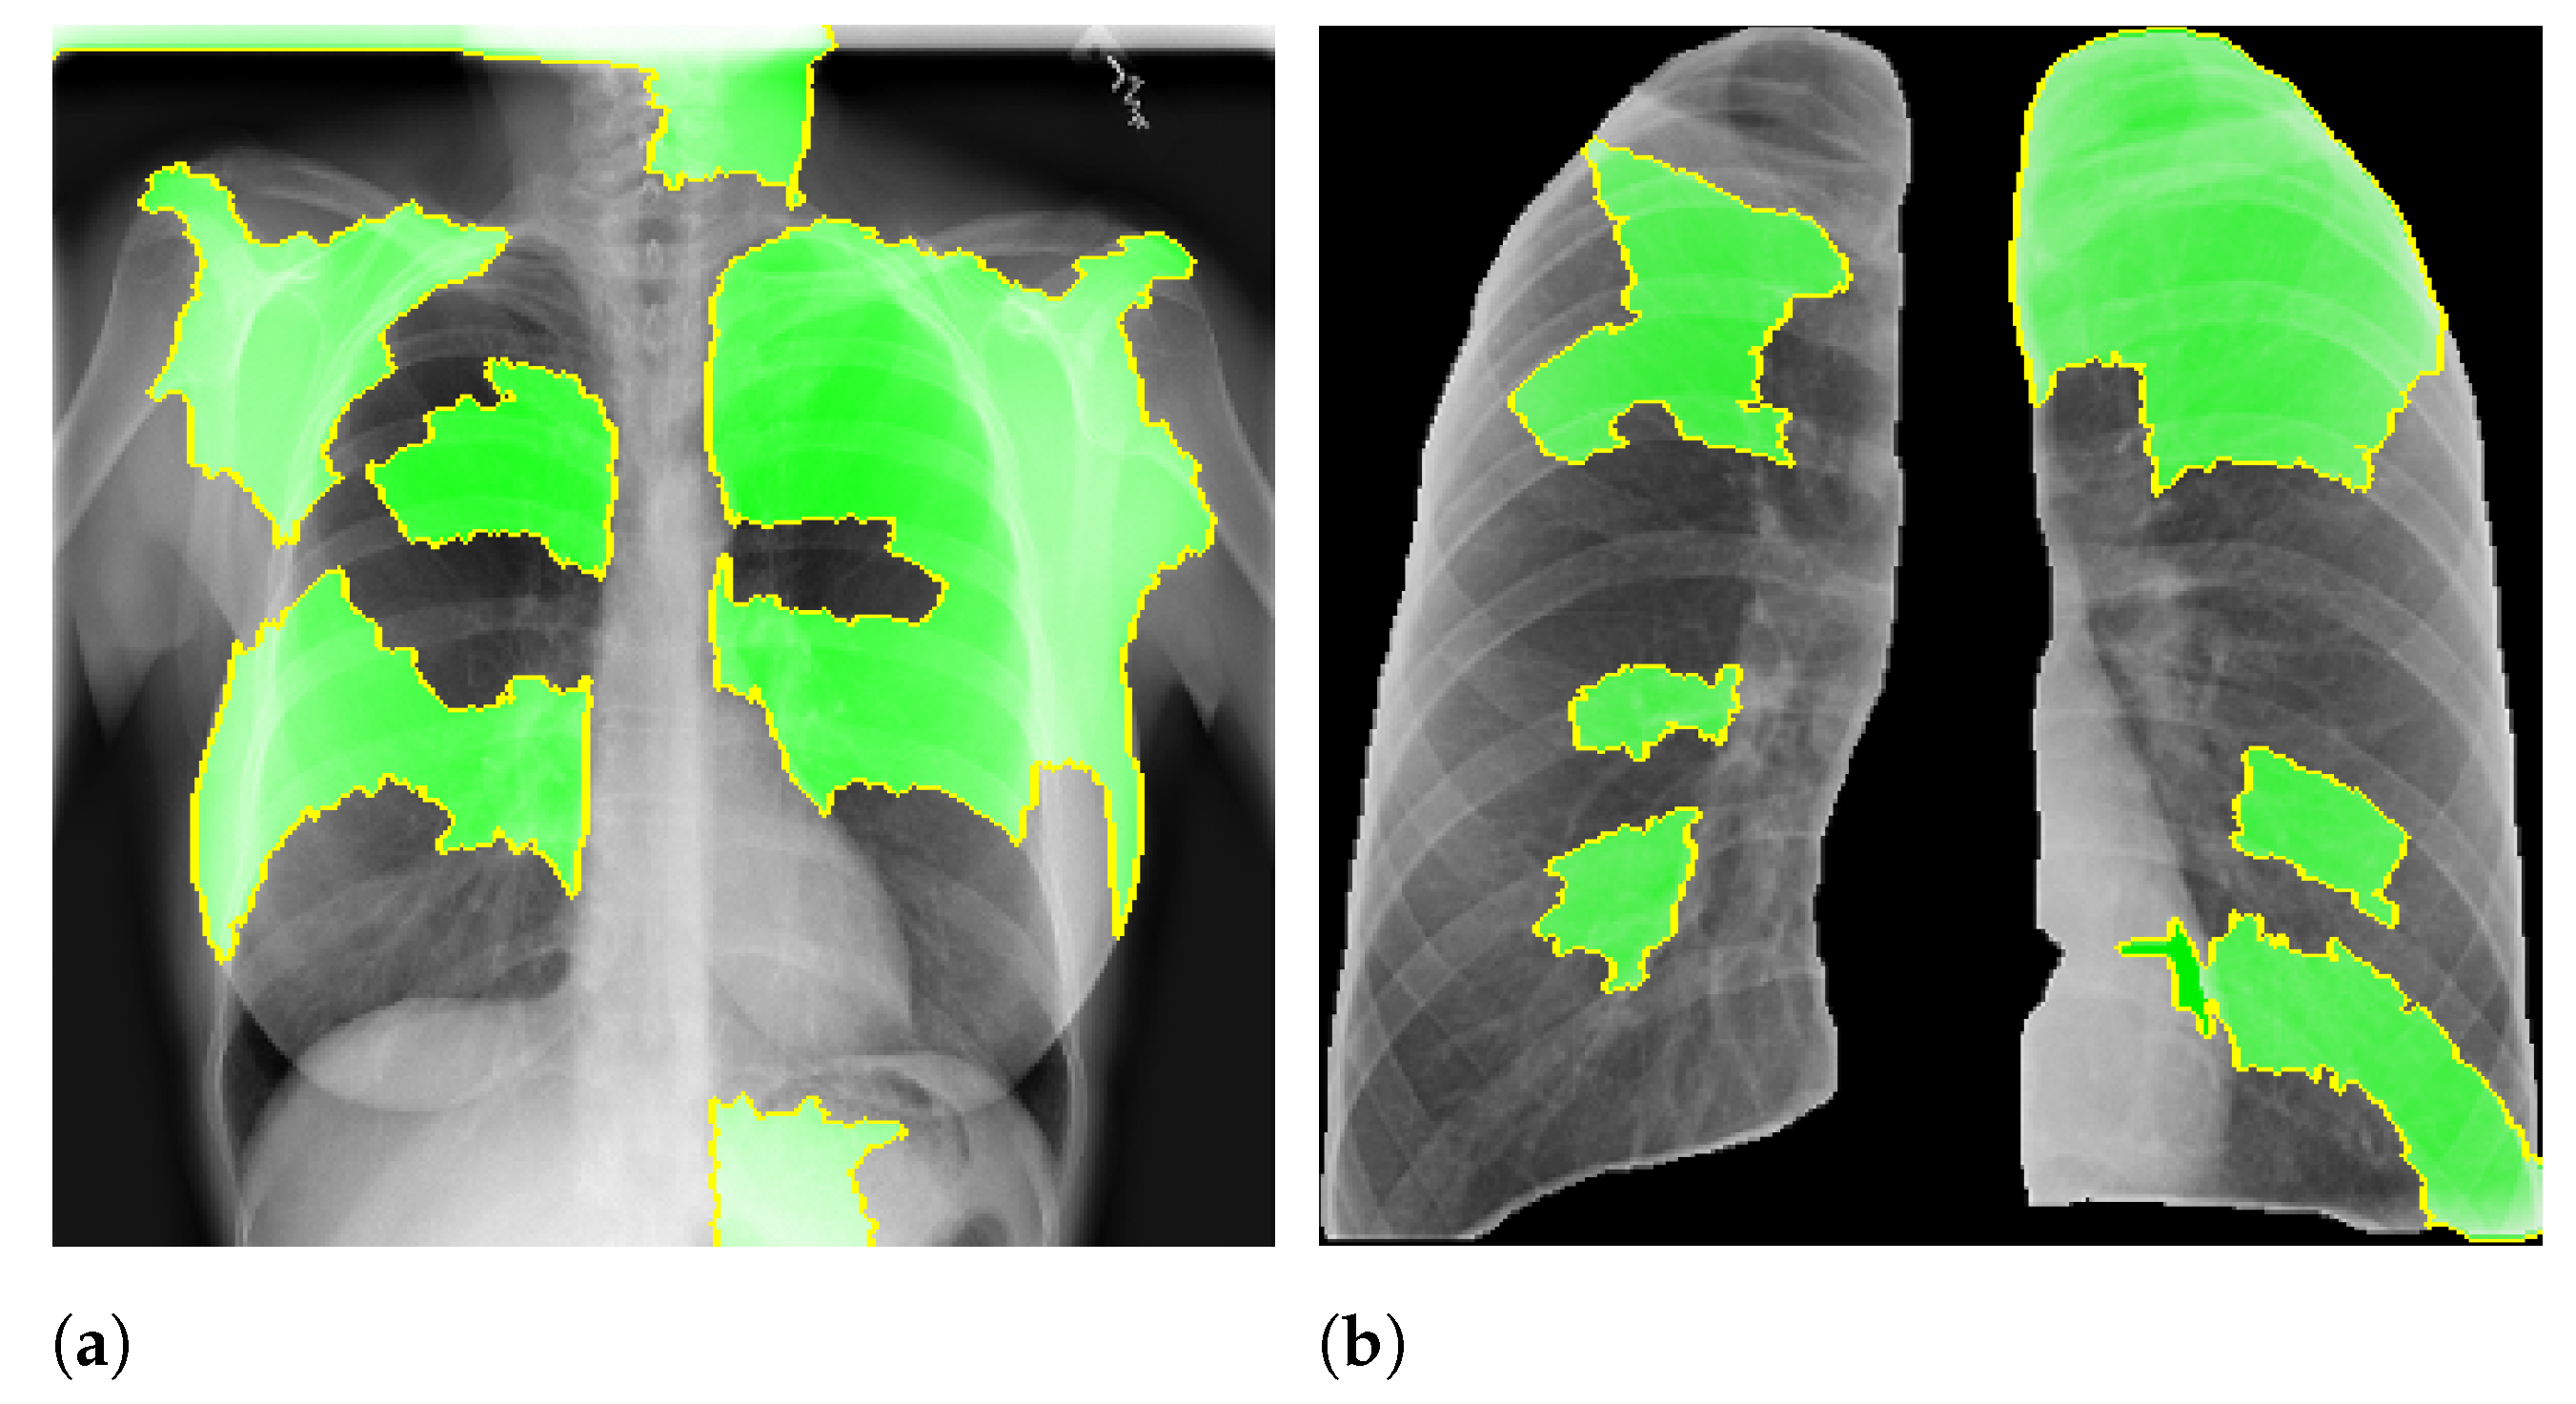

Figure 2 presents an example of lung segmentation.

Figure 2 shows an example of this process.

Figure 7 and

Figure 8 shows examples of important regions highlighted by LIME and Grad-CAM, respectively. In

Section 4, we will show that models trained using segmented lungs focus primarily on the lung area, while models trained using full CXR images frequently focus elsewhere.